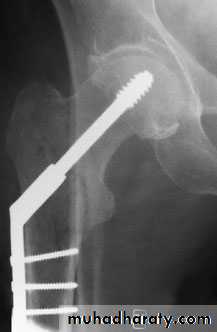

PLATE & SECROW FIXATIONDHS